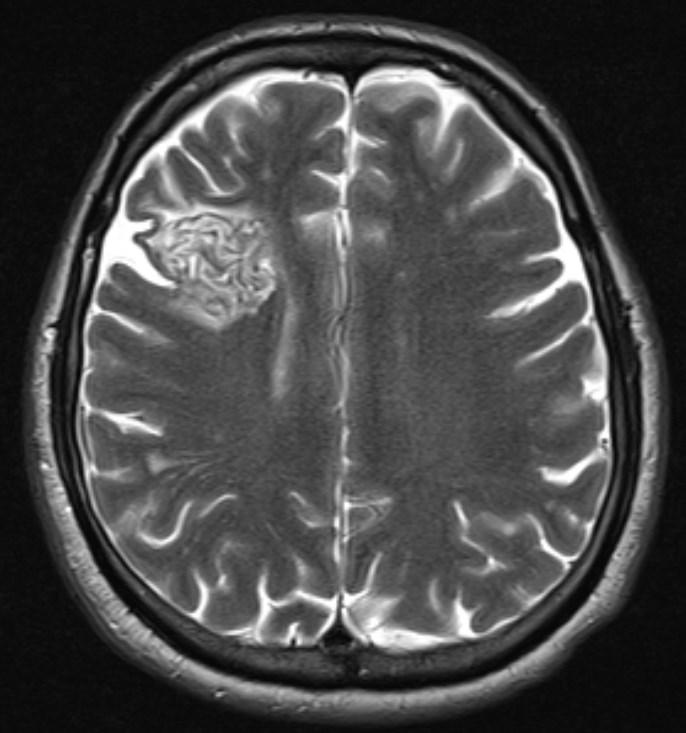

Answer: Primary hydatid cyst of right frontal lobe.

MR images revealed Gharbi type V hydatid cysts in right frontal lobe.

Gharbi classified hydatid cyst ultrasonographic images into 5 types: Type 1, walled, unilocular, anechoic; type 2, separated membranes; type 3, multisepta, daughter vesicles; type 4, heterogenic, hypo-hyperechogenic; type 5, calcification of a section of the wall or completely calcified (4). The cysts characteristically have three components: Pericyst, Exocyst, and Endocyst.